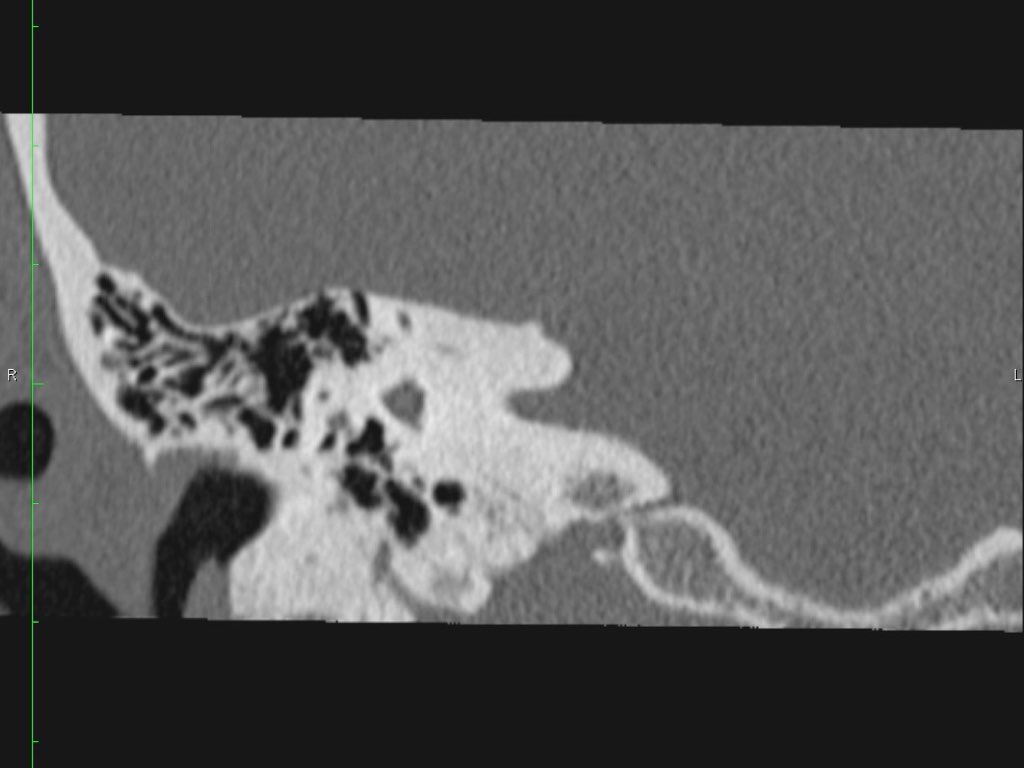

Hình ảnh một bệnh nhân có cholesteatoma.

Có một khối mô mềm ở vùng thượng nhĩ.

Lưu ý hình ảnh thủng màng nhĩ (mũi tên vàng) và bào mòn ống bán khuyên ngoài (mũi tên đỏ).

Scutum bị tù mòn.